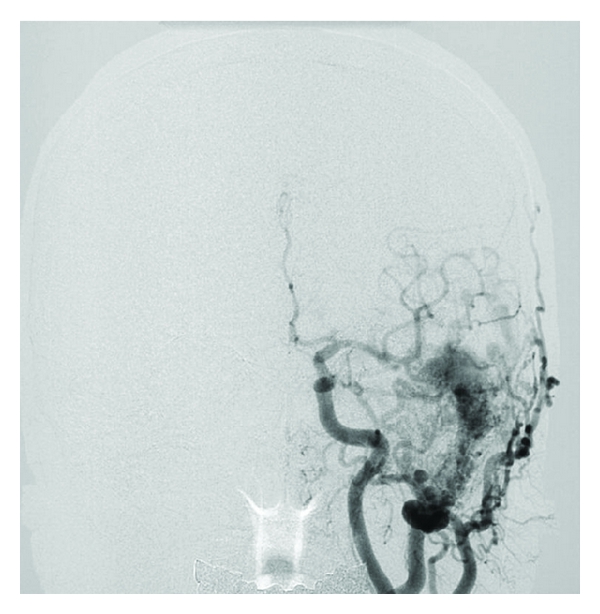

Part of this case has already been reported previously [2–4]. A 46-year-old male had been treated with antidepressants to depression at a local hospital for four years. The patient was temporarily laid off due to his depression. Afterwards, he became poor at ordinary conversation with his wife. Therefore, she took him to the local hospital. Because a cerebrovascular disease was suspected in the institute and the patient was recommended to consult neurosurgery, he came to our hospital on the same day as onset of the symptoms. On admission, the patient exhibited acalculia, finger agnosia, right-left disorientation, agraphia, and hemispatial agnosia. A CT scan was obtained immediately. Multiple high density spots were evident in a wide area of the left temporal, parietal, and occipital lobes on plain CT scan. They were thought to be dilated draining cortical veins. The left transverse-sigmoid sinus corresponding to the draining sinus also became larger than the right side on the CT scan [2]. A cerebral angiography was subsequently performed. A DAVF in the left transverse-sigmoid sinus with cortical vein reflux in the left temporal, parietal, and occipital lobes was demonstrated on the left common carotid artery angiogram. Its feeding arteries were the left occipital artery, posterior auricular artery, middle meningeal artery, and superficial temporal artery (Figure 1). After the examinations, the patient was admitted to the intensive care unit. In a former axial image of 3D-CT angiography arterial phase obtained after admission, abnormal vessels appeared in the left cerebral hemisphere including the left dorsolateral prefrontal cortex (DLPFC) (Figure 2). After the three endovascular surgeries [4], the DAVF including the cortical vein reflux disappeared on the angiogram (Figure 3). The patient did not experience any complications during and after these procedures, and his depression as well as Gerstmann’s syndrome was improved. The quantity of the antidepressants for the patient decreased after the treatment, and the patient returned to work without any antidepressant two years after the treatment.

(a)

(b)

(c)

(d)